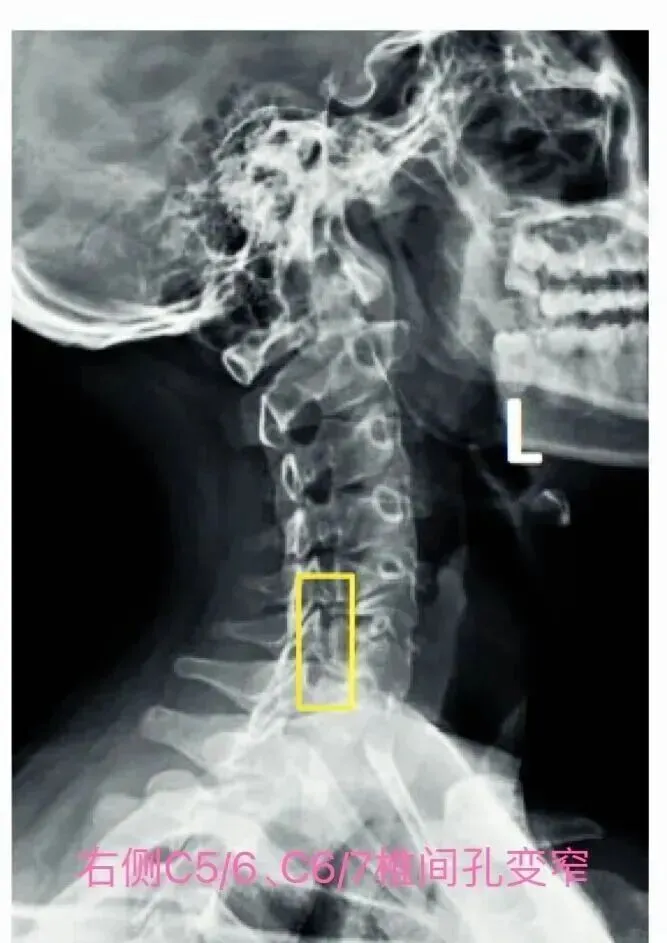

(三)斜位片观察要点:

2. 椎间孔观察: